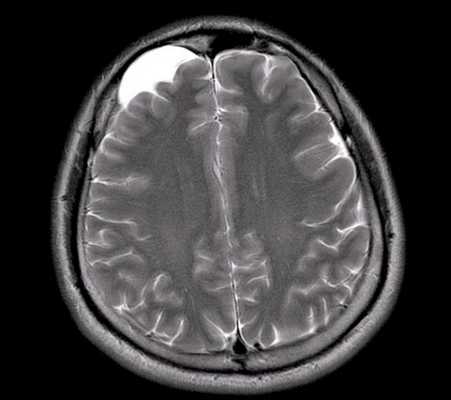

МРТ головного мозга. Арахноидальная киста полюса левой височной доли. Цветовая обработка.

Кисты головного мозга - это аномалии его развития. При МРТ в СПб мы видим задачу в дифференциальной диагностике с кистозными формами опухолей. При МРТ головного мозга некоторые виды кист, особенно дермоидные, сами напоминают опухоль.

Арахноидальные кисты представляют собой скопление ликвора между листками расщепленной паутинной оболочки. Арахноидальная киста обычно не сопровождается другими мальформациями. Незначительная часть арахноидальных кист имеет приобретенное происхождение - следствие лептоменингита, операции или кровоизлияния. Частота составляет около 1% от внутричерепных образований. Соотношение полов М:Ж, как 4:1. Типичная локализация - средняя черепная ямка (в области Сильвиевой борозды 50%), межполушарная щель, мосто-мозжечковый угол (11%), за скатом или на уровне четверохолмия (10%), в области червя мозжечка (9%), реже в области межножковой и предмостовой цистерн (3%), а также супраселлярной и хиазмальной цистерн. В зависимости от размера предложено делить кисты на 3 типа (Galassi, 2006), что однако, не имеет практического значения. Ретроцеребеллярная арахноидальная киста довольно часто встречаются за мозжечком и отличима от mega cisterna только по неизменённой задней черепной ямке. При МРТ головного мозга содержимое кисты чисто ликворное, стенки гладкие, чётко очерченные, внутри кисты могут быть перегородки. Мелкие арахноидальные кисты очень трудно увидеть при МРТ головного мозга. Меняя ширину окна и его уровень на Т1-зависимых МРТ изображениях можно заметить, что киста чуть светлее ликвора. Дифференциальная диагностика с эпидермальными кистами лучше осуществляется с помощью МРТ последовательности FLAIR. На них при МРТ головного мозга эпидермальные кисты становятся яркими, в отличие от гипоинтенсивных арахноидальных. Вероятно, вариантом арахноидальной кисты является нейроэпителиальная киста, которая при МРТ головного мозга имеет типичное расположение в области хориоидальной щели.